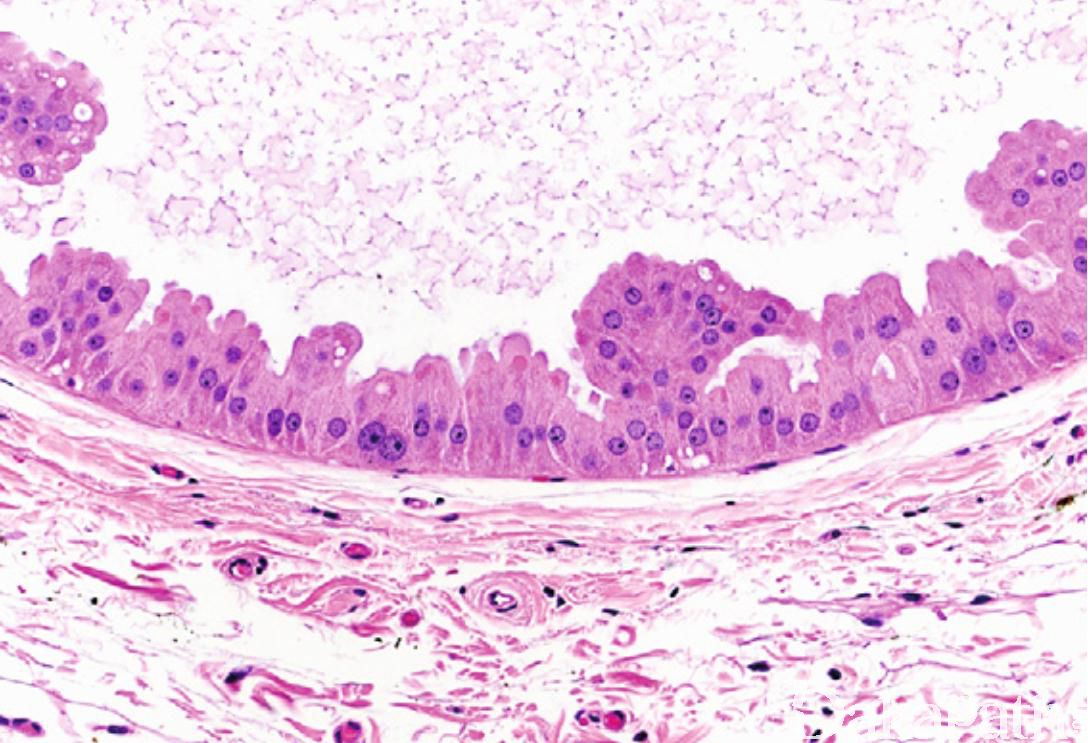

乳腺乳头状大汗腺增生

Breast Papillary Apocrine Hyperplasia

大汗腺囊肿的被覆上皮出现乳头状结构或上皮细胞簇。

乳头状大汗腺增生的形态学有 3 种类型:

简单型:大汗腺囊肿衬覆的上皮局灶增生细胞达 3 层或 3 层以上,形成小丘状细胞团,细胞团的基部比顶部宽,在囊腔内常不相互接触;

复杂型:乳头较高,顶端比基部稍宽,在腔内常互相接触,形成分支乳头状;

高度复杂型:乳头细长,2 ~ 3 层细胞宽度,在腔内广泛分布,形成狭长的连拱结构,与其他乳头相互缠绕,此型常伴有不典型大汗腺型导管增生,此时应诊断为乳腺不典型大汗腺型导管增生或乳腺大汗腺型导管原位癌。